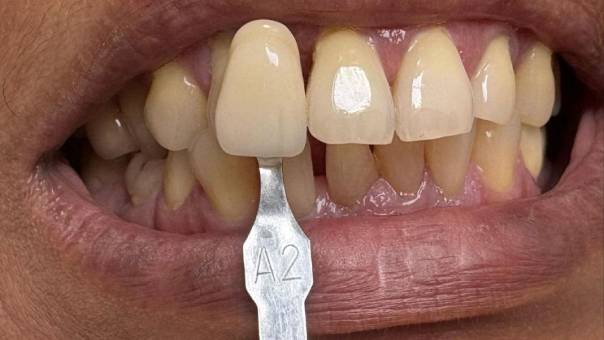

Shade selection

The Final Touch: The patient opted for a Zirconium bridge, known for its strength, durability, and natural appearance. The result was a seamless, natural-looking smile transformation.